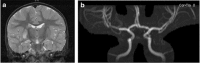

Stroke is as common as brain tumor in children. The etiology of childhood arterial ischemic stroke (AIS) appears to be multifactorial, resulting from the interaction between genetic predisposition and environmental triggers. The risk factors for AIS in children are markedly different from the atherosclerotic risk factors in adults. Trauma and infections have been identified as associations in previous studies and are exposures of particular interest because of their increased prevalence in the children. The aim of this review article is to provide an overview of the research studies that have addressed the role of infections and trauma in pediatric AIS.